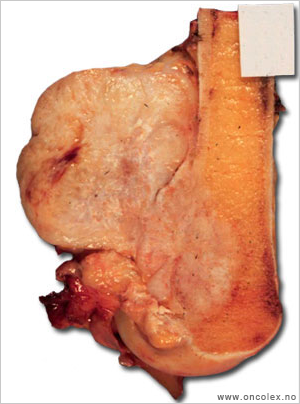

| Femurpreparat med osteosarkom. |

Klassisk osteosarkom

Klassisk osteosarkom ses hos unge i alderen 10–30 og sitter i metafysen i lange rørknokler, typisk rundt kneet og øverst i overarmen. Tumor viser malignt utseende celler som produserer osteoid og ben med forkalkninger. Det kan i tillegg ofte påvises områder med kondroblastisk og/eller fibroblastisk utseende. Dersom man ikke får representativ biopsi kan man feilaktig stille diagnosen kondrosarkom eller fibrosarkom på et slikt materiale.